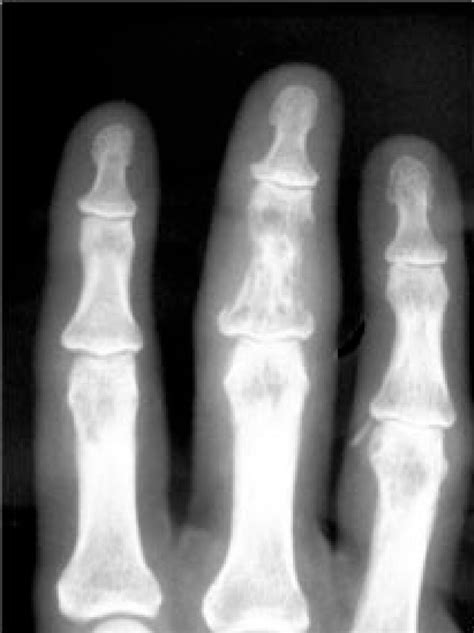

Osteonecrosis de los Maxilares (ONM)

Desde la comercialización de fármacos que actúan sobre el remodelado óseo se han registrado numerosos casos de osteonecrosis de los maxilares (ONM), pero hasta hace poco solo se habían descrito casos de ONM asociados a la administración de bifosfonatos. Con la introducción de nuevos agentes antirresortivos han aparecido varios casos de ONM asociados a denosumab.

La osteonecrosis mandibular (ONM) es una reacción adversa conocida para denosumab. La etiología de la ONM es desconocida, si bien se han identificado determinados factores de riesgo que favorecen su desarrollo: tratamiento previo con bisfosfonatos, edad avanzada, higiene bucal deficiente, procedimientos dentales invasivos, existencia de determinadas comorbilidades.

La patogénesis de la ONM asociada a agentes antirresortivos no está completamente definida. Se ha establecido la hipótesis de que una inhibición exagerada de la osteoclastogénesis y una disminución rápida del recambio óseo añadido a un daño tisular macrofágico, podrían desencadenar el desarrollo de osteonecrosis. La cirugía dentoalveolar, las extracciones dentales, una mala higiene bucal y las prótesis dentales son factores de riesgo independientes para la ONM.